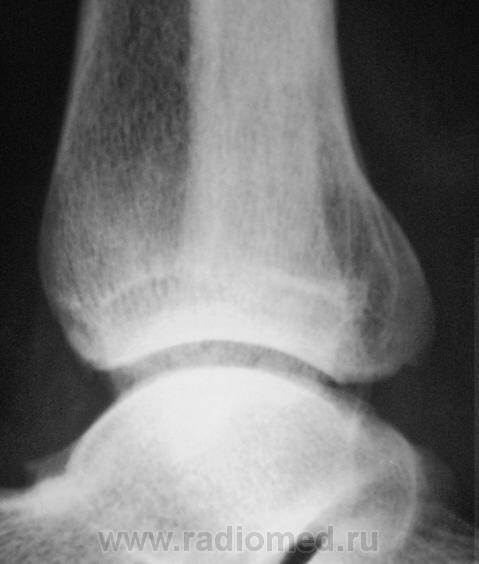

Пациент, в течение последних 2-х лет, жалуется на боли в нижней трети голени. Сегодня, хирургом, пациентка направлена на рентгенографию костей дистальной трети голени и голеностопного сустава. Что посоветуете уважаемые коллеги?

А что здесь советевать? Межберцовый неоартроз, вероятно, травматического генеза. Косой перелом н/л с признаками неполной консолидации. Попробуйте при производстве боковых снимков г/ст с-ва ( при травме) приподнимать пятку на 2-3 см.

А, если, предположить, что травмы (переломов) не было? Тогда как?

Неоартроз между экзостозами? А что это за вздутие м/б кости на уровне неоартроза и пятнистость наружного кортикала? Следствие хронической воспалительной реакции?

Соглашусь с Вами по поводу экзостозов.

Доброй ночи! Разволокнение коркового слоя, нечеткий очаг деструкции. Правда, нет секвестра. Если на увеличении не пригрезилось, то и линейный периостит. Вообще-то ответ был интуитивный, без логических обоснований. Ошиблась?

Какая-то непонятная структура костной ткани в области задней лодыжки.

Некоторая порозность, вероятно, нарушение трофики

В области внутренней лодыжки тоже пороз.